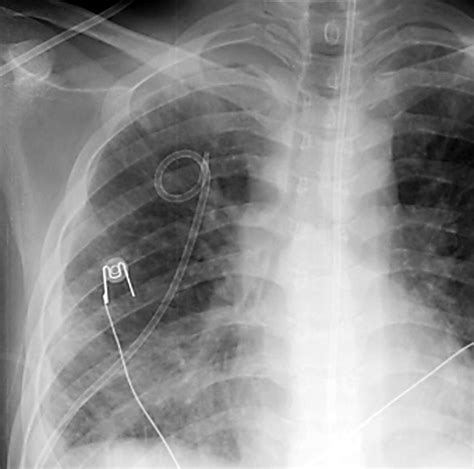

• Pigtail Chest Tube Placement: Insert the Pigtail Chest Tube over the guidewire and advance it into the pleural space. Remove the guidewire and secure the tube in place.

• Connection to Drainage System: Connect the Pigtail Chest Tube to a drainage system, such as a pleural drainage unit, to facilitate fluid or air removal.

• Dressing and Securing: Apply a sterile dressing around the insertion site and secure the tube with sutures or adhesive tape.